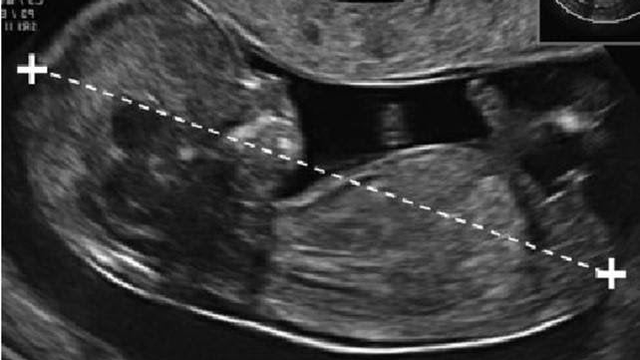

Suốt thai kỳ, thai phụ sẽ trải qua nhiều xét nghiệm và siêu âm để theo dõi sức khỏe thai nhi. Một trong những siêu âm quan trọng là đo nếp gấp ở gáy thai nhi, giúp phát hiện sớm nguy cơ dị tật nhiễm sắc thể ở bé. Trong bài viết dưới đây Nhà thuốc Long Châu sẽ giúp bạn tìm hiểu những thông tin về đo nếp gấp da gáy ở thai nhi, mời bạn đọc cùng theo dõi.